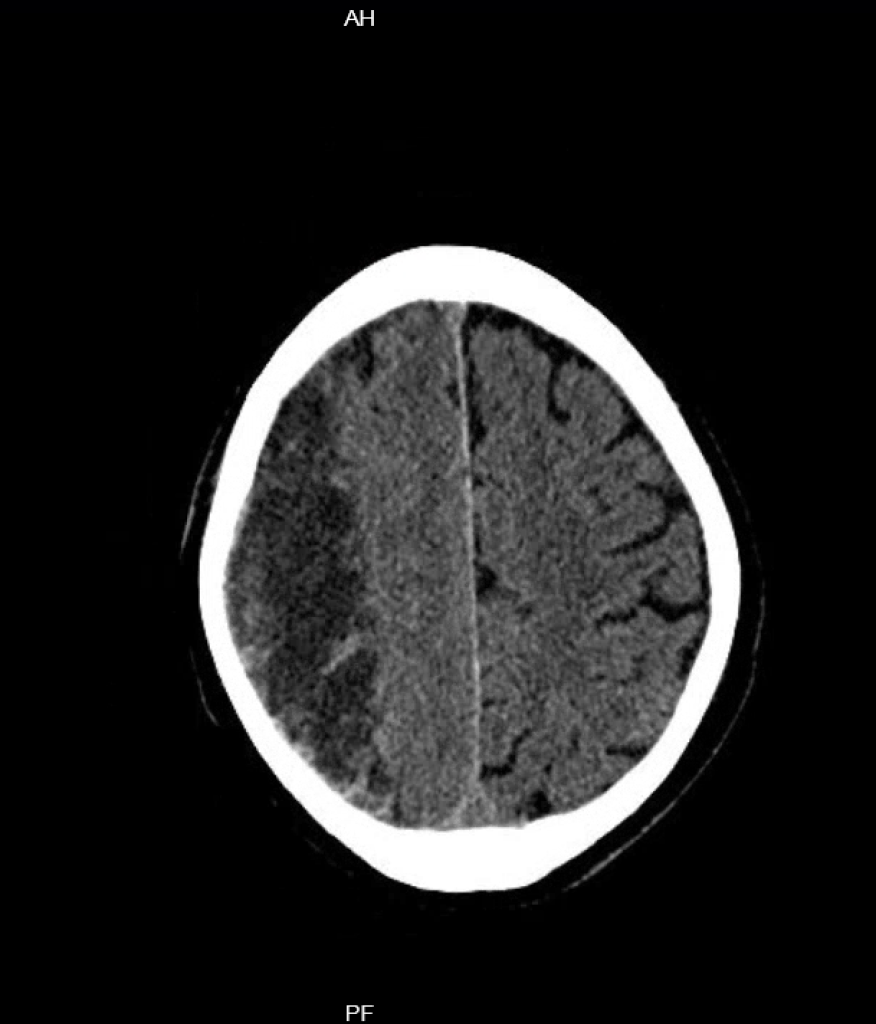

Subduralhämatom

Subduralhämatome können chronisch im Rahmen einer Sickerblutung oder akut – dann oft bei bestehender Antikoagulation – durch den Einriss von Brückenvenen entstehen. Da das Gehirn langsame Druckänderungen und Masseverschiebungen viel besser toleriert als akute können chronische Subduralhämatome viel größere Ausdehnungen erreichen, bevor sie überhaupt Symptome verursachen.

Während es bei akuten Subduralhämatomen relativ klare OP-Indikationen für eine Bohrlochtrepanation gibt (Hämatomdurchmesser > 10 mm, Mittellinien-Verlagerung > 5 mm, GCS < 9 Punkte, GCS-Abfall um 2 Punkte, Anisocorie und Hirndruck > 20 mmHg), ist das bei chronischen Subduralhämatomen anders. Hier kommt es zu – sich oft im Verlauf auch selbst resorbierenden – Sickerblutungen, eine relative OP-Indikation besteht bei einem symptomatischen Subduralhämatom und einer bildmorphologischen Hirnparenchym-Kompression. Hier müssen aber immer Nutzen und OP-Risiko bei den oft hochaltrigen, multimorbiden und in der Regel hochgradig delirgefährdeten Patienten abgewogen werden, auch weil das Rezidivrisiko bei chronischen Subduralhämatomen mit ca. 30% sehr hoch ist. Mit der Embolisation der A. meningea media steht zudem – momentan (auch auf Grund der fehlenden aktuellen Leitlinie) nur in Studien durchführbare – interventionelle Behandlungsmöglichkeit zur Verfügung. Idee der Embolisation ist es, das oft sehr fragile Kapillargeflecht, was in die Brückenvenen mündet zu veröden.